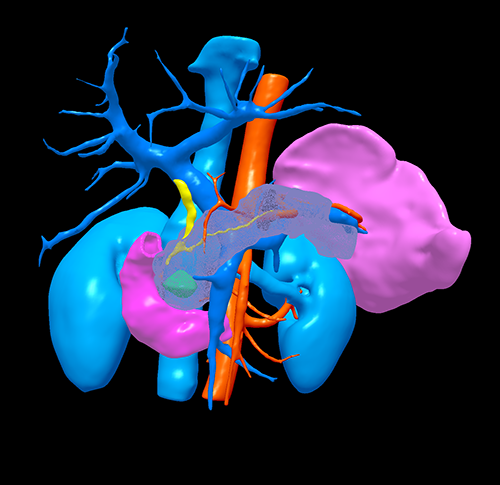

肿块型慢性胰腺炎----胰十二指肠切除